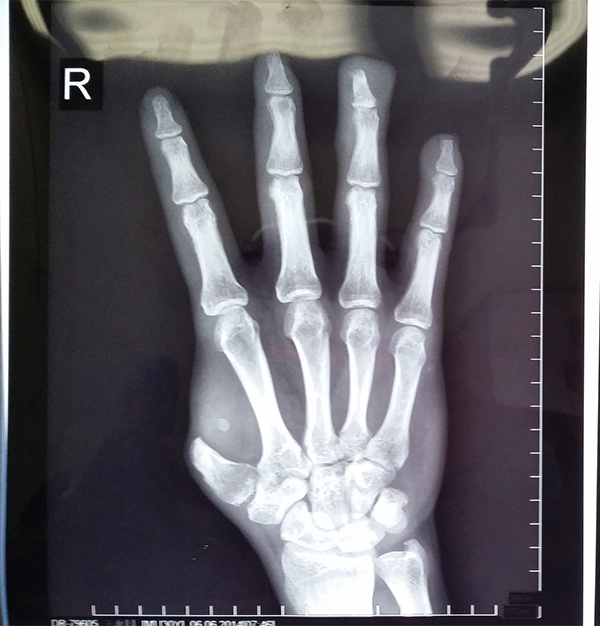

示指长手指再造(1)

示指长手指再造(2)

示指指尖修饰性再造